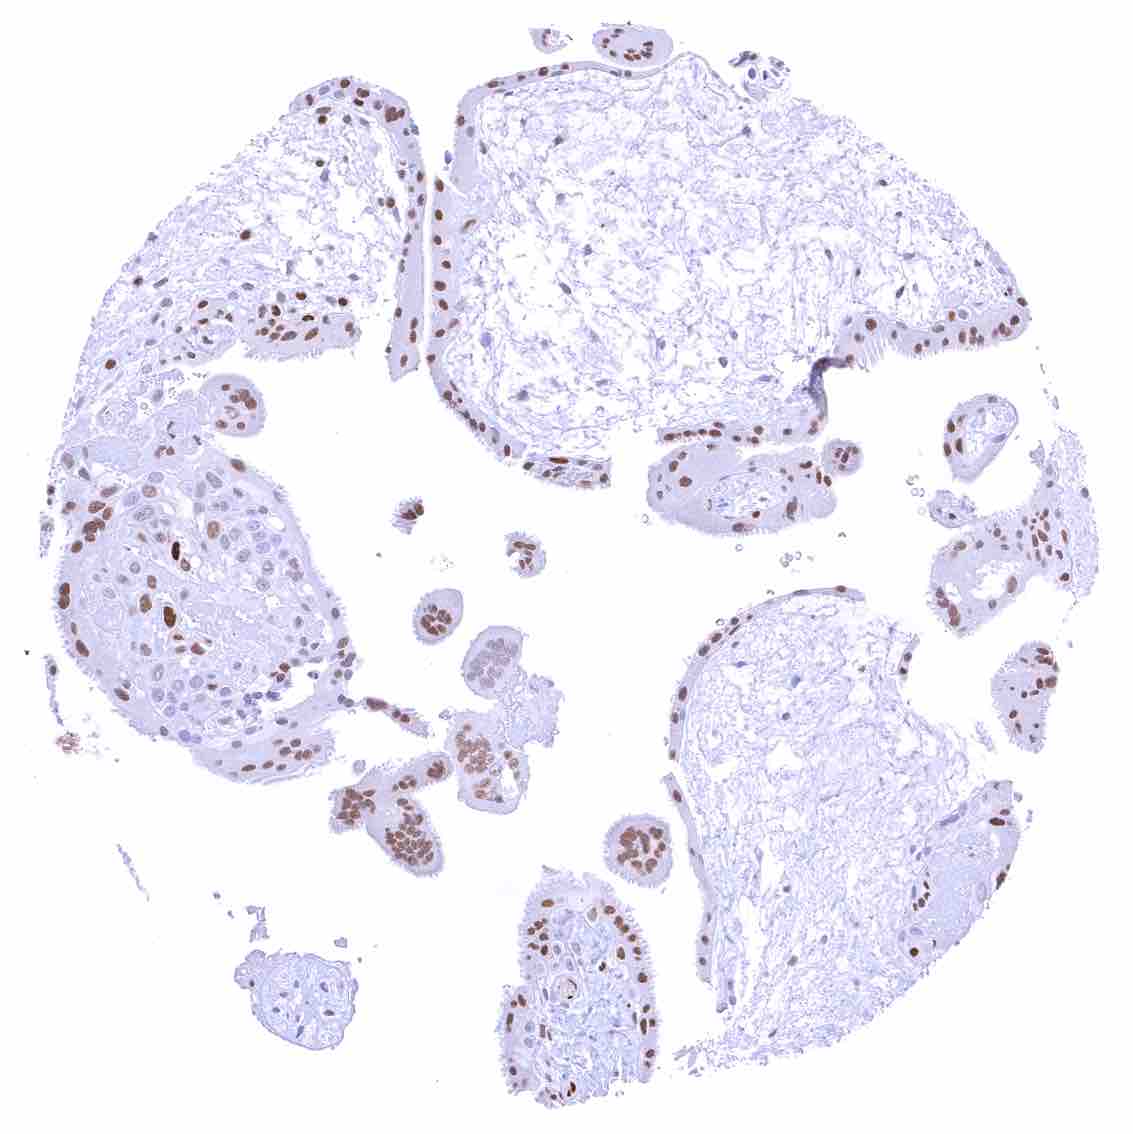

Placenta, early – Strong p27 staining of all nuclei of the syncytiotrophoblast.